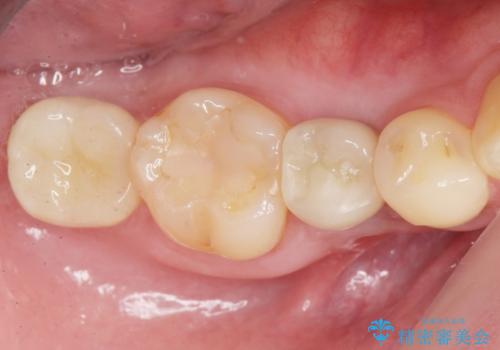

自然な仕上がりと咬み心地に喜んで下さいました。

「低予算でしっかりした治療を受けることができた」とご満足頂けました。

インプラントの種類:アルファタイト

クラウンの種類:オールセラミッククラウン スタンダード